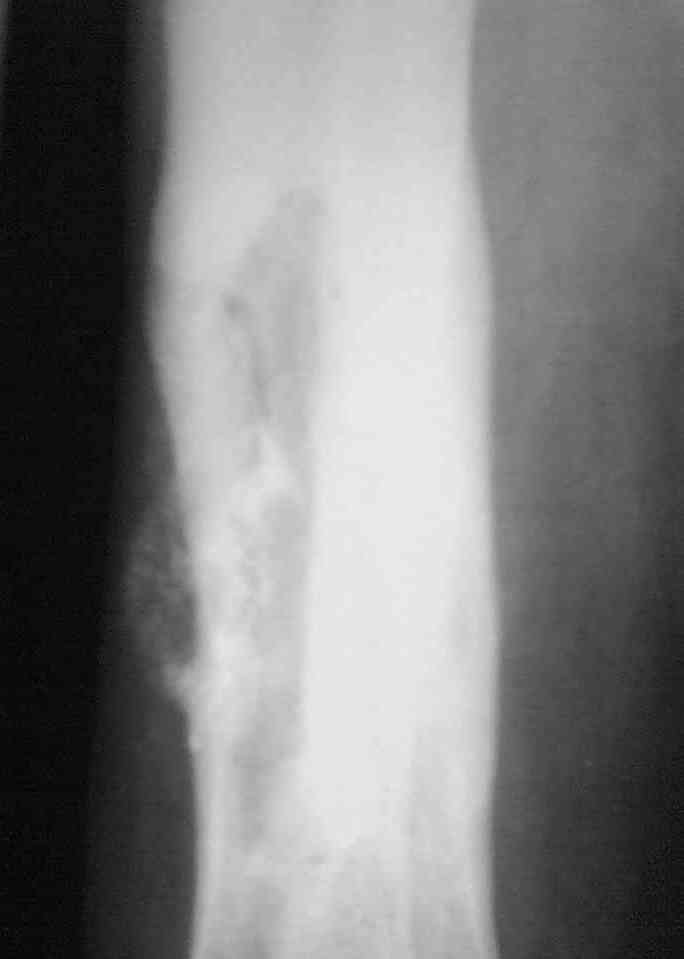

Выкладываю снимки в хронологическом порядке. Снмки все какие есть у больного.